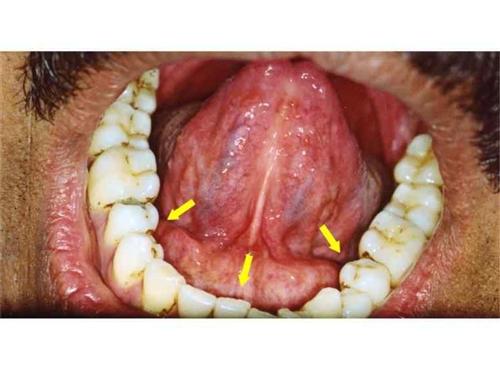

間隙主要為脂肪組織,一旦感染,很容易液化。咬肌間隙感染:咬肌間隙內出現感染,可有化膿,咬肌局部腫脹,有深壓痛。·個,我想問大家多間隙感染都有哪些間隙感染才能被稱為叫做口底多間隙?...